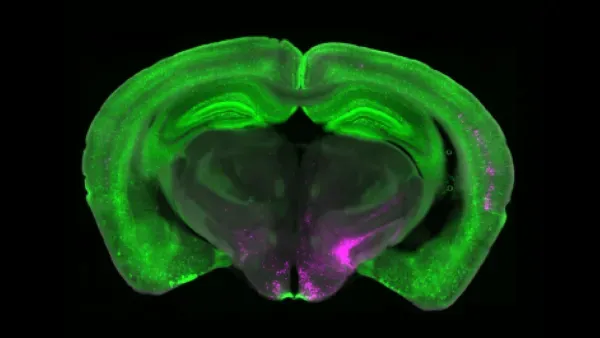

Các nhà khoa học phát hiện mạch não tắt đau mãn tính ưu tiên sinh tồn